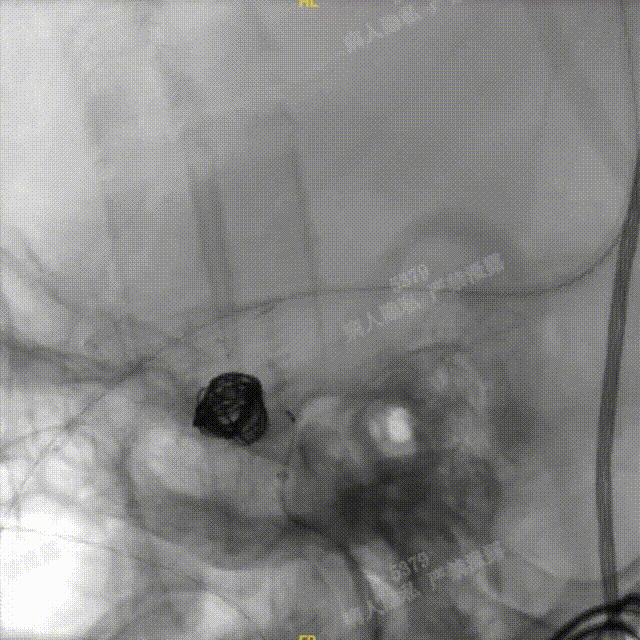

Headway™ 27 156cm微导管内输送FRED 4518血流导向密网支架,系统远端精准定位于预计着陆区以远3-5mm,回撤微导管原位释放支架,头端锚定在颈内末端处。

正位

确认支架远端定位于计划位置,预估近端可完全覆盖动脉瘤颈,且锚定距离充足。继续平衡释放系统,确保支架整体充分打开且贴壁良好后,解脱支架。

造影确认,载瘤动脉通畅、支架远端分支血流通畅、支架贴壁良好、动脉瘤内造影剂滞留。

正、侧位造影及术后CT复查结果观察,载瘤动脉通畅、支架贴壁良好、动脉瘤内造影剂滞留、颅内未见明显异常。